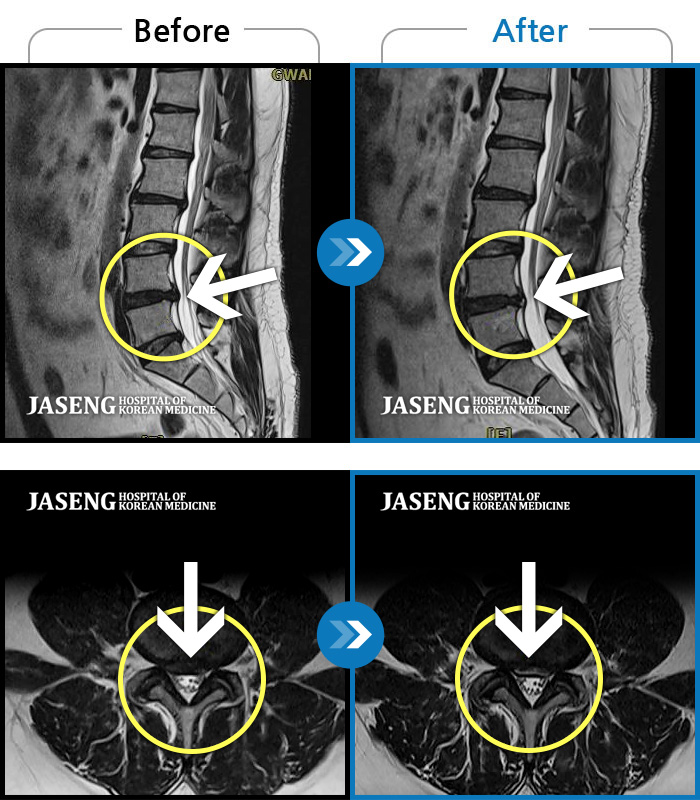

Before

After

허리 통증과 우측 허벅지 통증 및 저림 증상 지속되어 내원하셨습니다.

2022.08.20 ~ 2024.11.08